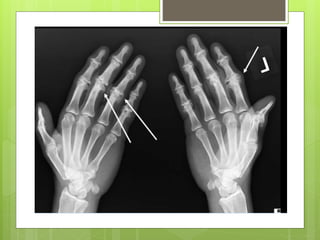

 Primary OA:

 It occurs in old age, mainly in the weight

over the trapezio- metacarpal joint of the

thumb and distal interphalangeal joints of the

fingers.

Hand

 Joint fusion

 Joint replacement

 Primary OA: It occurs in old age, mainly in the weight bearing joints (knee and hip). Can also occur over the trapezio- metacarpal joint of the thumb and distal interphalangeal joints of the fingers.